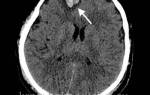

• МРТ для выявления повреждений внутренних органов, спинного мозга, локализации кровоизлияний или некротических очагов